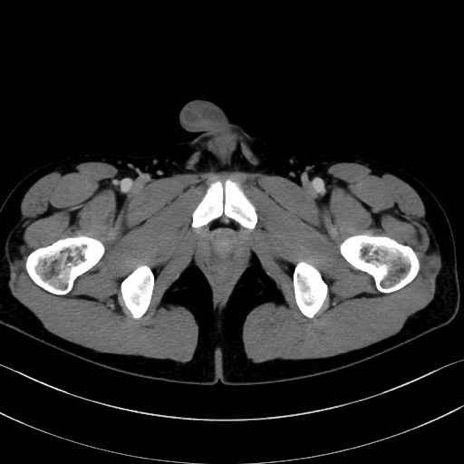

精嚢(seminal vesicle)のCT画像における解剖

症例

【症例】20歳代 男性 スクリーニング